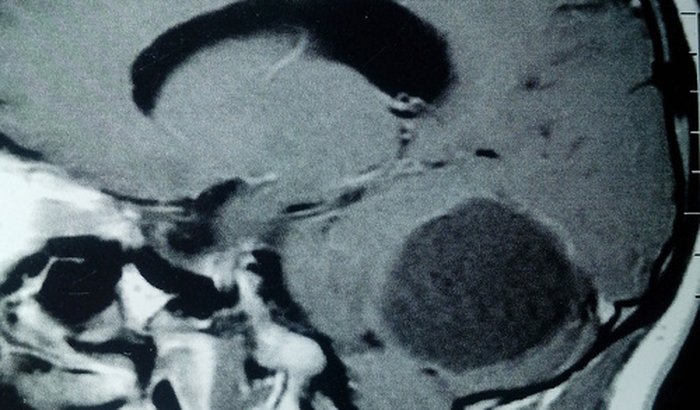

Tenho 26 anos e a um ano e meio luto contra um câncer cerebral , tratamentos, exames , se você puder ajudar ver tudo

Tenho 26 anos e a um ano e meio luto contra um câncer cerebral , tratamentos, exames , se você puder ajudar